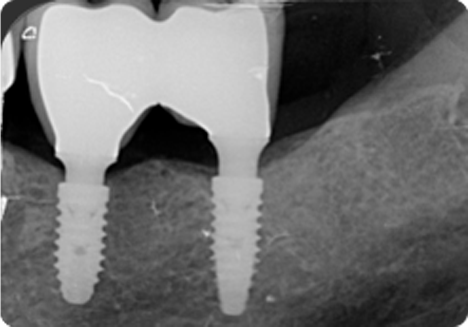

GEOMETRÍA DEL IMPLANTE

Núcleo cónico expansivo de diámetro creciente desde su zona apical hasta su zona coronal, favoreciendo su inserción en áreas con poco volumen óseo. Doble paso de rosca y ápice neutro para una colocación rápida y una óptima estabilidad primaria, ideal para cargas inmediatas y cirugías post-extracción.